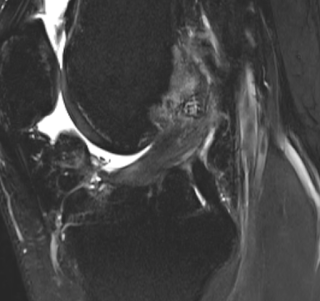

vice-versa is 20 percent. The chance of instability like below can be ruleout by an mri/or a good ultrasound